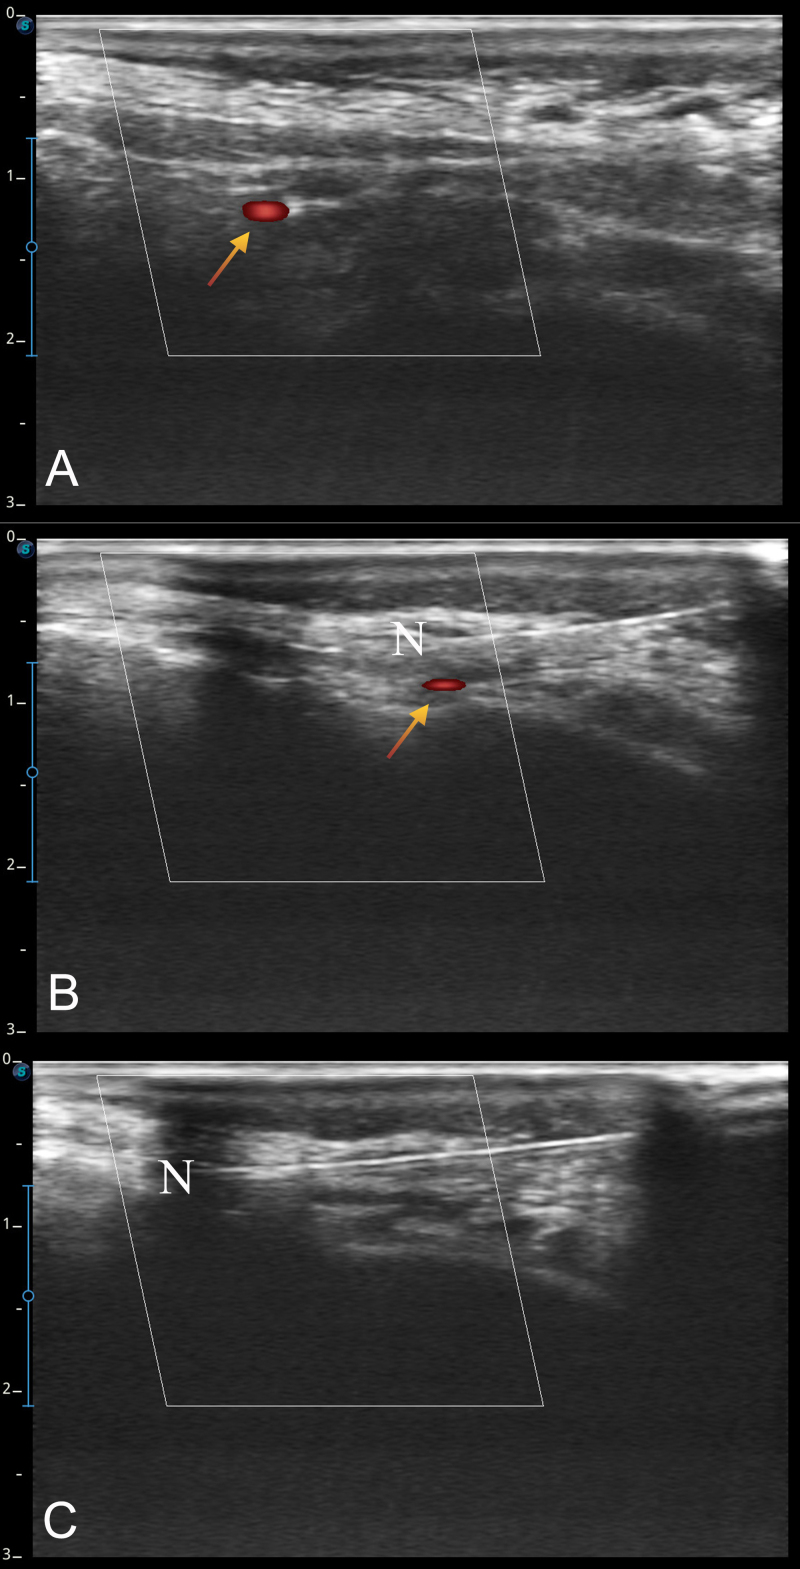

The aim of this study was to compare the effectiveness of greater occipital nerve (GON) block and pulsed radiofrequency (PRF) treatment in chronic migraine patients. Seventy patients admitted to the Neurology and Algology outpatient clinic between September 2023 and December 2023 and diagnosed with chronic migraine according to The International Classification of Headache Disorders 3rd Edition (ICHD-3) criteria were included in the study. Patients were randomized into 2 groups to receive ultrasound-guided repeated GON block and PRF. Visual Analog Scale (VAS) scores for pain relief and Migraine Disability Assessment (MIDAS) scores for disability were recorded before the procedure and at 1st and 6th months after the procedure. In both groups, 35 patients with greater occipital nerve (GON) block, 32 patients with GON PRF, the pain scores at 1st and 6th months post-procedure were significantly lower compared to before the procedure (p < 0.001, p < 0.001, respectively). VAS scores were significantly lower in the PRF group than in the GON block group at 6th month (p = 0.009). In both groups, post-procedural MIDAS scores at 1st and 6th months were significantly lower compared to before the procedure (p < 0.001, p < 0.001, respectively). In the GON PRF group, MIDAS scores at 6th month were significantly lower than MIDAS scores at 1st month (p < 0.001). MIDAS scores were significantly lower in the PRF group compared to the GON block group at 6th months (p < 0.001).Interventional procedures such as GON block and PRF are safe and effective methods in chronic migraine. PRF is a better alternative to GON block in chronic migraine with longer effectiveness.

Abstract Image